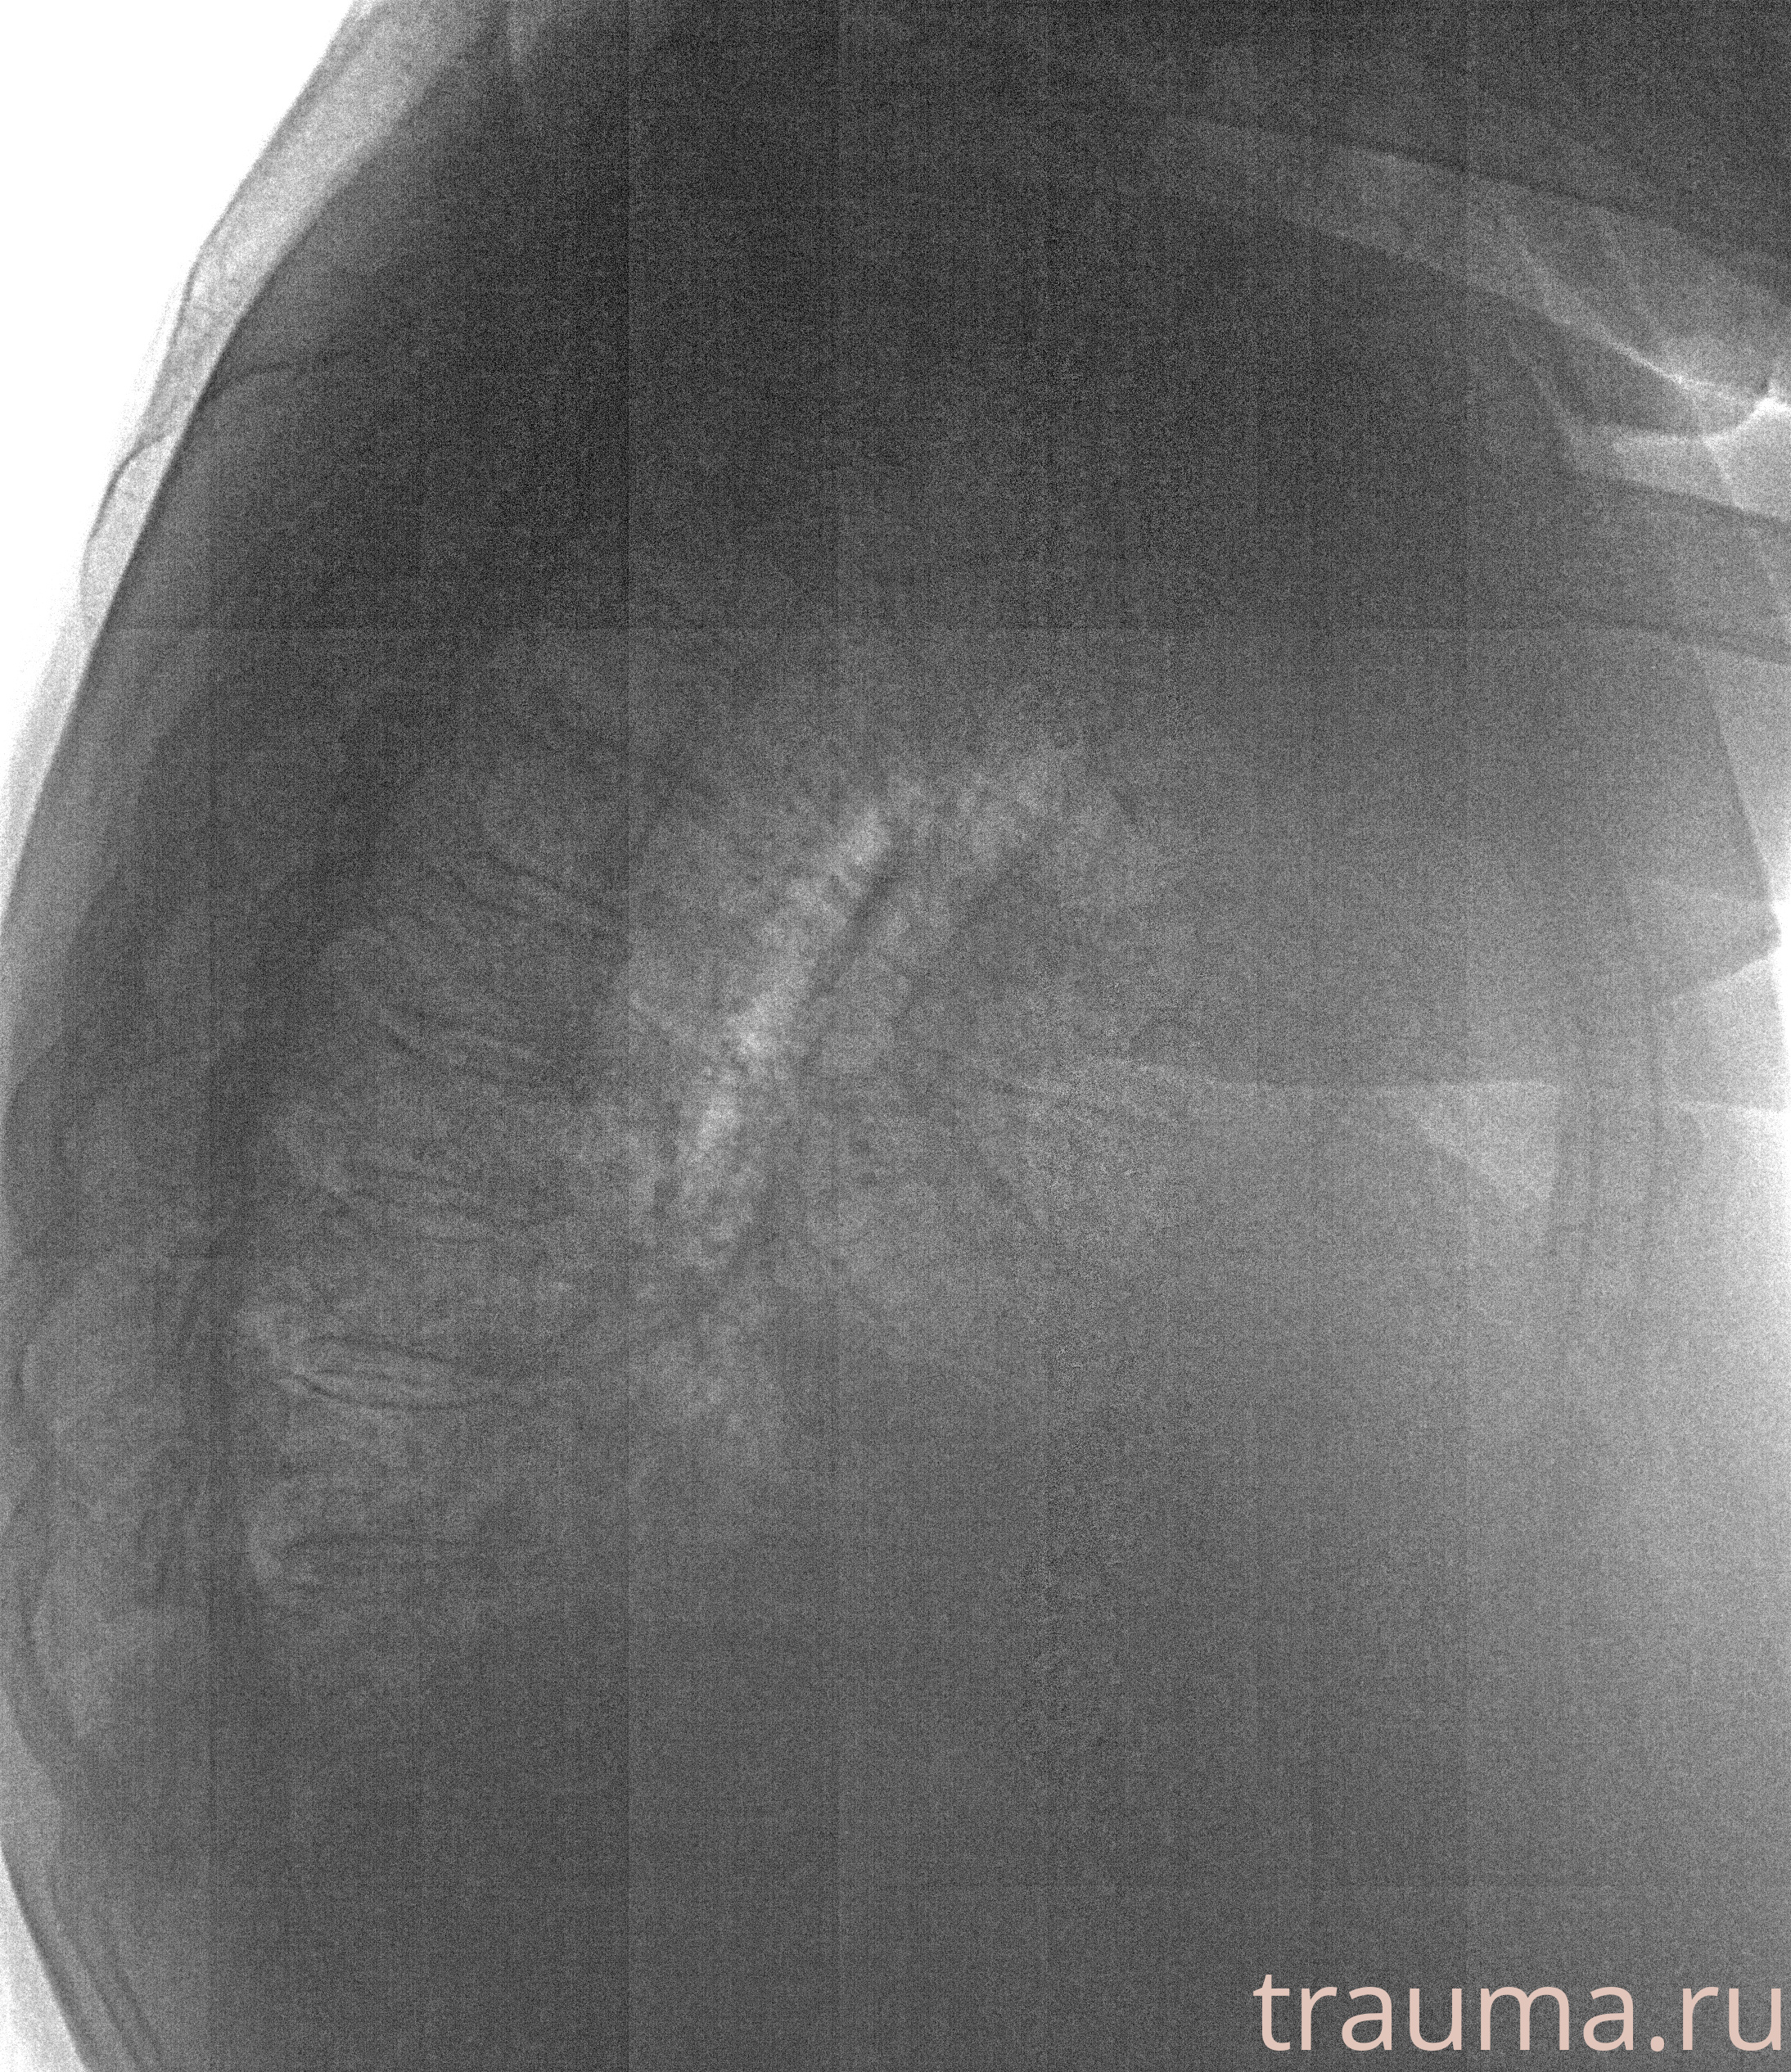

Рентгенограммы

Рентген на дому: по вашему адресу приезжает врач-рентгенолог, травматолог-ортопед с мобильным рентгеновским аппаратом, проводит диагностику травмы или заболевания, делает необходимые рентгенограммы, дает рекомендации по дальнейшему лечению. Получить качественные снимки в домашних условиях возможно благодаря уникальной методике, разработанной МосРентген Центром для института  Склифосовского

при переломе шейки бедра и пневмонии от компании МосРентген Центр - партнера Института имени Склифосовского